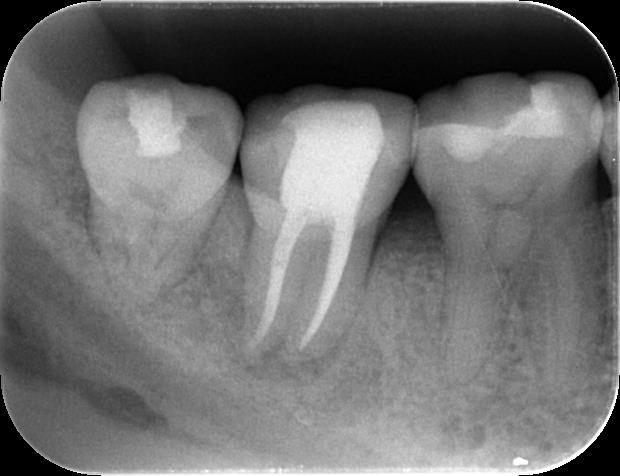

治療後の経過をレントゲン写真で追跡したところ、治療開始から3ヶ月後には、根の先にあった黒い影(骨が溶けていた部分)が大幅に縮小し、骨が再生してきている様子が確認できました。そして、半年後には病変は消失し、健康な骨組織に置き換わっていました。

一般的に、保険診療での根管治療では、病変が治癒するまで半年以上にわたって違和感が続くケースも少なくありません。当院の精密根管治療は、徹底した感染管理と精密な処置により、より確実でスピーディーな治癒を目指すことができます。

2025年現在、治療から数年が経過していますが、再発もなく、患者さんは今もご自身の歯で、何不自由なく食事を楽しまれています。